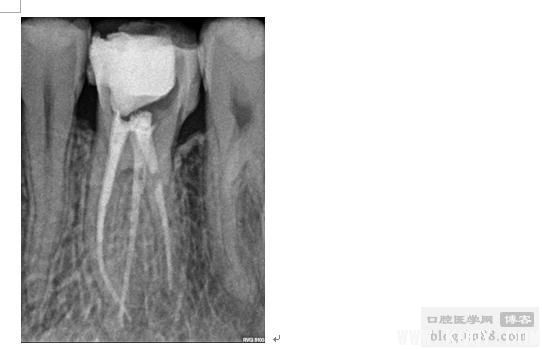

插针片(MB与MB2属于2-1分型) 试尖片(NI-TI预备后)

热牙胶充填后

(值得强调的一点:一定要拍试尖片,这对后期充填是否到位及是否完美非常重要)